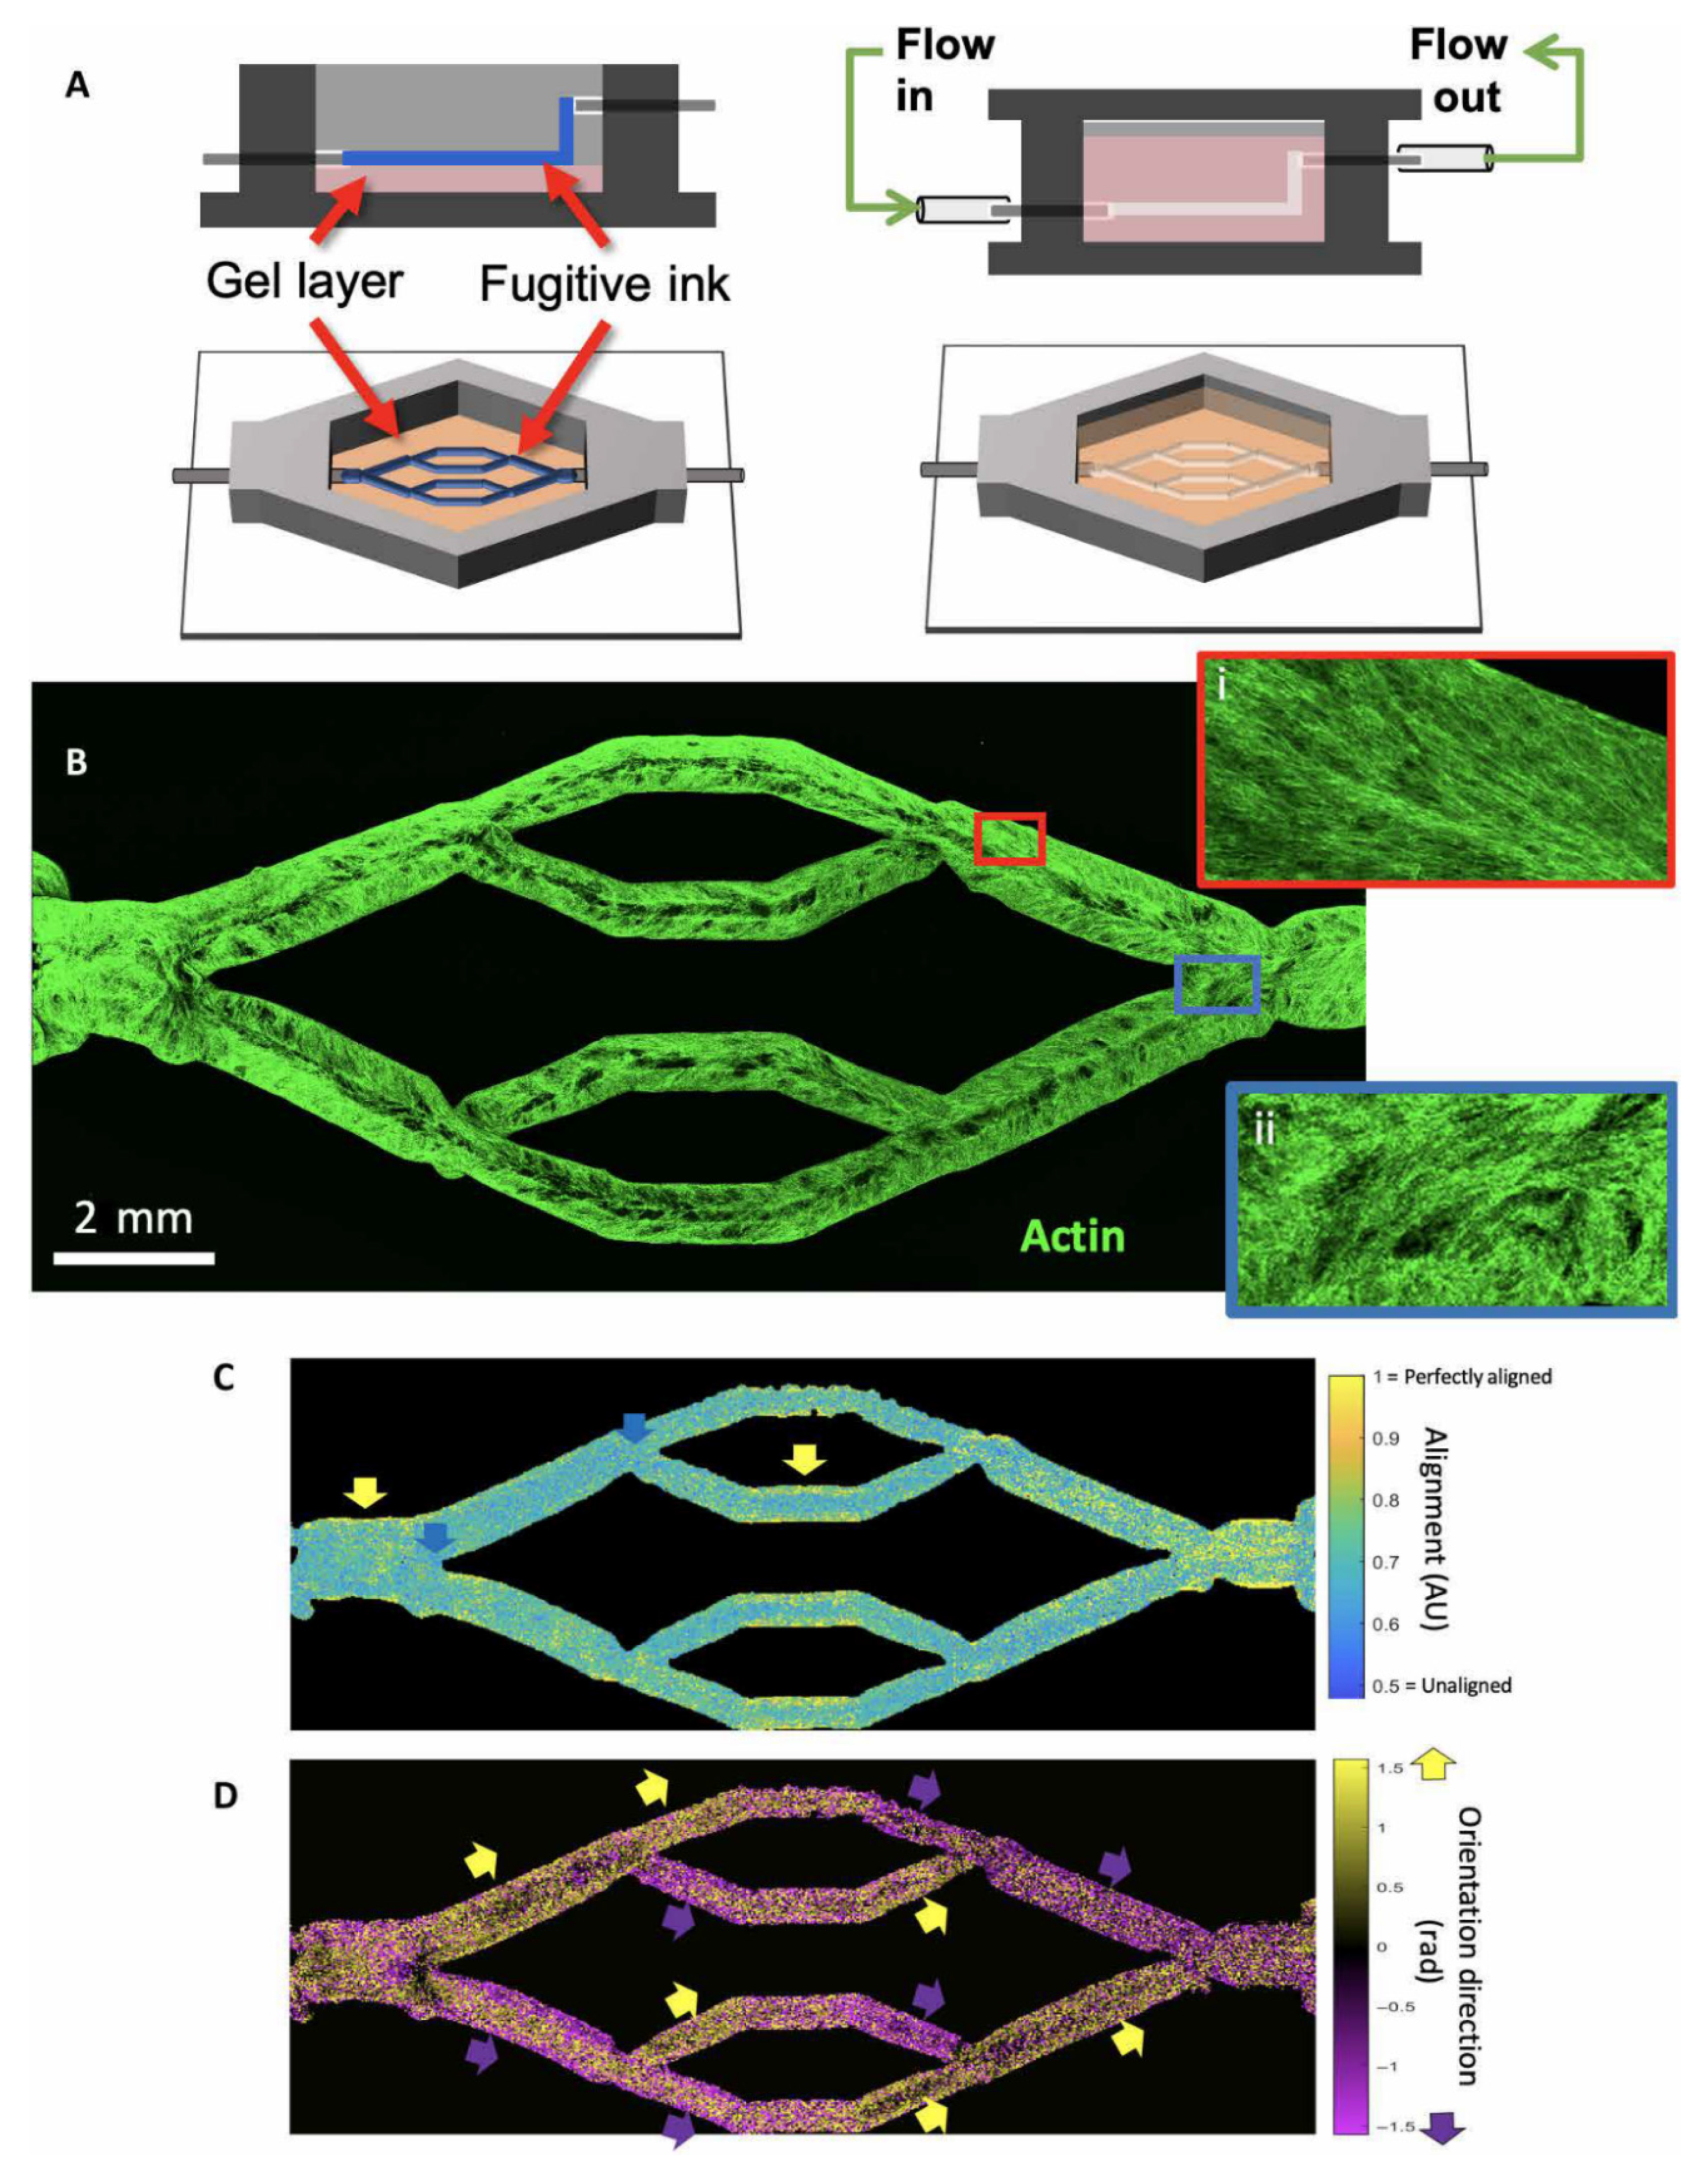

3.6. 3D Bioprinting in Cardiovascular Disease

- Miller, J.S.; Stevens, K.R.; Yang, M.T.; Baker, B.M.; Nguyen, D.-H.T.; Cohen, D.M.; Toro, E.; Chen, A.A.; Galie, P.A.; Yu, X.; et al. Rapid casting of patterned vascular networks for perfusable engineered three-dimensional tissues. Nat. Mater. 2012, 11, 768–774. [Google Scholar] [CrossRef] [PubMed]

- Kolesky, D.B.; Homan, K.A.; Skylar-Scott, M.A.; Lewis, J.A. Three-dimensional bioprinting of thick vascularized tissues. Proc. Natl. Acad. Sci. USA 2016, 113, 3179–3184. [Google Scholar] [CrossRef] [PubMed]

- Redd, M.A.; Zeinstra, N.; Qin, W.; Wei, W.; Martinson, A.; Wang, Y.; Wang, R.K.; Murry, C.E.; Zheng, Y. Patterned human microvascular grafts enable rapid vascularization and increase perfusion in infarcted rat hearts. Nat. Commun. 2019, 10, 584. [Google Scholar] [CrossRef]

- Hynes, W.F.; Pepona, M.; Robertson, C.; Alvarado, J.; Dubbin, K.; Triplett, M.; Adorno, J.J.; Randles, A.; Moya, M.L. Examining metastatic behaviour within 3D bioprinted vasculature for the validation of a 3D computational flow model. Sci. Adv. 2020, 6, eabb3308. [Google Scholar] [CrossRef]